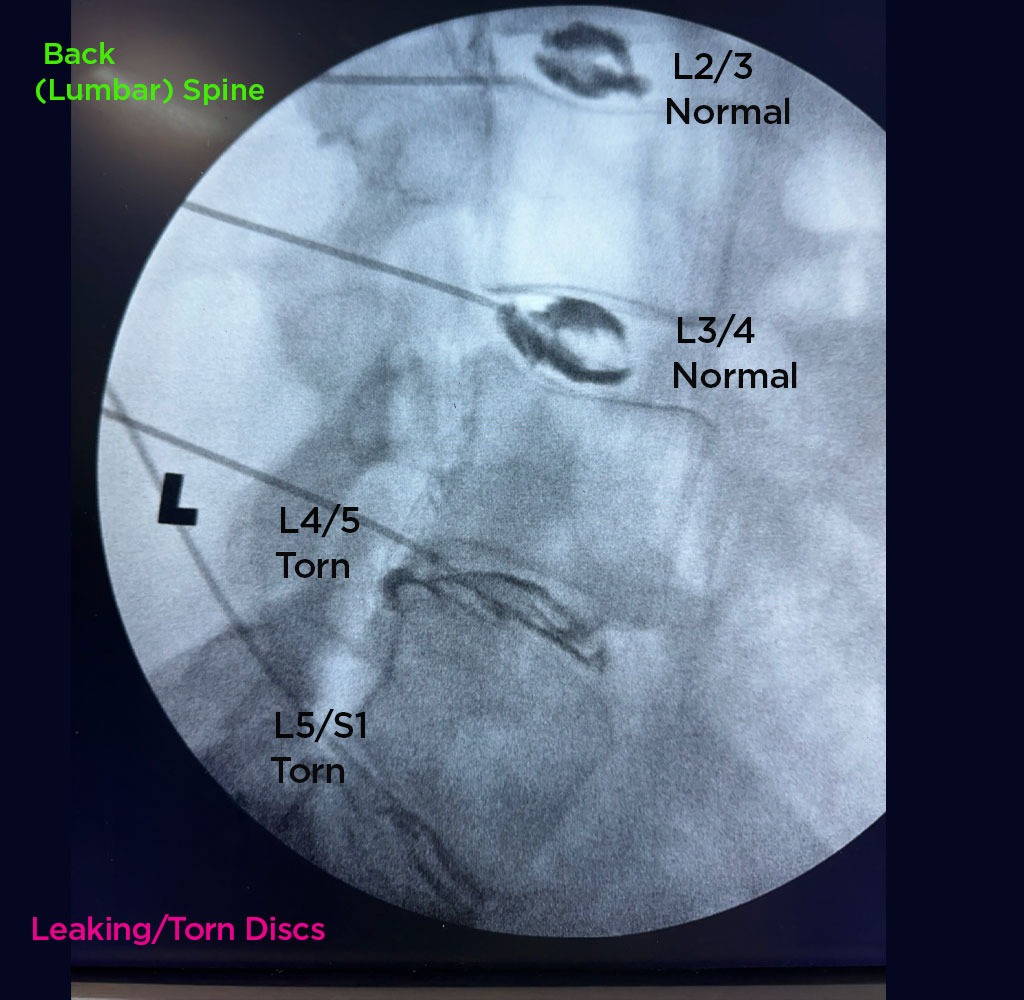

Annulargram™ Gallery

This gallery contains Annulargram images.

The Annulargram is a pain-free test and a crucial part of the DISCSEEL Procedure that identifies even the most subtle tears in spinal discs that MRI and discography cannot.

During the Annulargram, every disc in the region is tested to address current and future pain issues by finding even the most subtle annular tears. With the Annulargram, damaged spinal discs are pinpointed and precisely treated with Fibrin, leaving all healthy discs as they are.

Tears in spinal discs cannot be seen on MRI nor discography. As shown: leaky discs are only visible on the Annulargram.